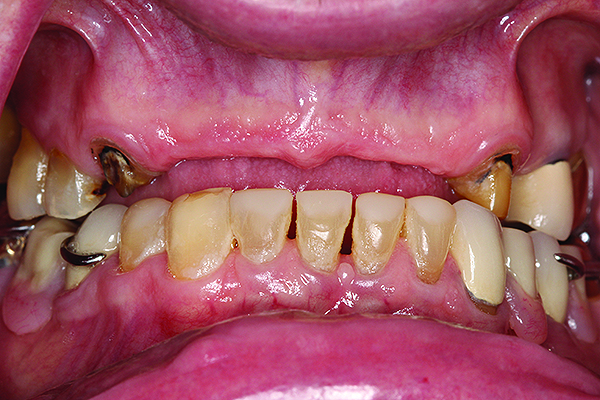

A 63-year-old African-American female presented at the University of North Carolina General Dentistry Student Clinic with a chief complaint that she was missing posterior teeth on both arches and said she would like to replace them (Figure 8).

The patient was concerned about esthetics because she was a school teacher. Her dental history revealed that she had removable partial cobalt chromium dentures that no longer fit and she had not used them for a long period. Her medical history at the initial examination revealed that she had type 2 diabetes mellitus, hypertension, and hyperlipidemia, all of which was controlled. However, she had no medical contraindication for dental care or oral surgical procedures.

The patient was presented with multiple treatment options to address her dental problems, including cast-metal partial dentures, acetal resin flexible partial dentures, and implants to replace the missing teeth and provide a first-molar occlusion. The patient initially opted for implants. During the planning phase for the implant therapy, the patient was hospitalized due to her diabetes and her physician advised against this first choice. Thus, the patient’s treatment plan was modified, and she consented to receiving acetal resin RPDs versus cast-metal RPDs due to her esthetic concerns.

A conventional RPD treatment protocol started with designing the RPDs and was followed by tooth and mouth preparation and final impressions. The RPD frameworks were fabricated using acetal resin (Myerson DuraCetalTM, www.duracetal.com) by Drake Precision Dental Laboratory in Charlotte, North Carolina (Figure 9).

Fig 8. Intraoral pre-operative photograph showing multiple missing posterior teeth in both arches.

Figure 8